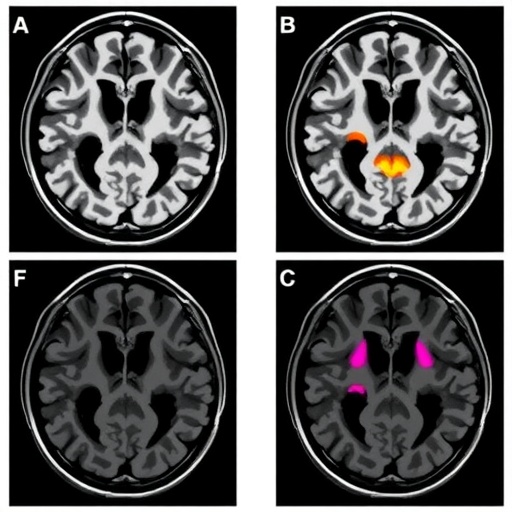

Neonatal MRI offers unparalleled insight into the intricacies of early brain injury, capturing hypoxic lesions, ischemic strokes, hemorrhages, and cerebral edema that cannot be fully appreciated through clinical exam alone. By translating complex imaging data into measurable scores, clinicians gain a powerful predictor that aligns well with the neurological developmental landscapes unfolding during infancy and beyond. The systematic review meticulously evaluated the strengths and weaknesses of each score, highlighting variability in regional specificity and imaging sequences utilized, yet underscoring an overarching predictive consensus.